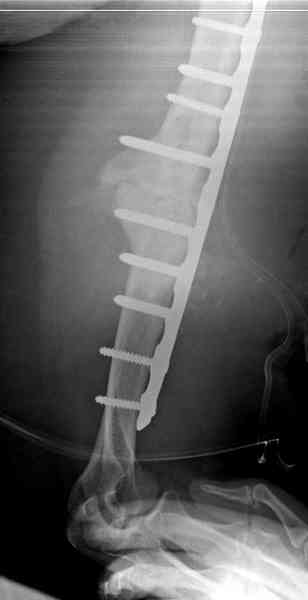

Как видно из выступлений коллег, способы фиксации

ложного сустава плеча могут быть различными, кто-то предпочитает аппаратом Илизарова (Соломин), пластинами (Волна) или интрамедуллярным гвоздем (Челноков).

Когда разбирался случай на сайте, и у нас была больная с похожей патологией, ложный сустав после поперечного перелома, леченного год назад где-то и кем-то в другом месте.

Первичную пластину убрали недели 6 назад из переднего оригинального доступа, и из-за подозрительности тканей вокруг пластины, решили провести реконструкцию поэтапно.

Хотя сам не стороннник применения более массивных

имплантов для плеча, но для этого случая сделали

исключение. На снимке 4А диаметр мягких ткани около 20 см, при весе больной более 135 кг, и также выступление Андрея Волны подстегнуло к применению более массивной 4.5 мм локинг пластины.